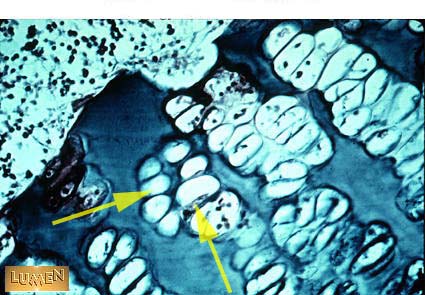

What cells are these?

Chondrocytes